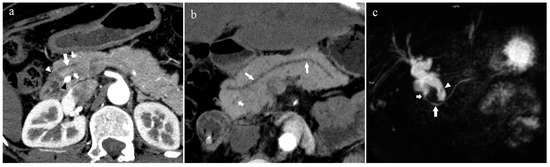

There were 109 patients in the variant group. The PD (type 4) was the most common pancreatic variant (6.2%, 50/808), including type 4b (3.5%, 28/808, Figure 6), complete PD (type 4a) (1.6%, 13/808, Figure 7), and incomplete PD (type 4c) (1.1%, 9/808, Figure 8). The frequency of type 3a was 0.6% (5/808, Figure 9), and that of reverse PD (type 3c) was 3.6% (29/808). The frequency of type 2 was 2.4% (19/808), including type 2a (1.5%, 12/808) and type 2b (0.9%, 7/808, Figure 10). Anza pancreatica (type 5) was relatively rare (0.7%, 6/808), including type 5a (0.6%, 5/808) and type 5b (0.1%, 1/808).

Figure 6.

Type 4b. A 46-year-old male patient with hilar cholangiocarcinoma. (a): MIP [45 keV MEI (+)] shows that the MPD (long arrow) flows into the MiP and extends to the tail. APD is not shown. The initial part of the common bile duct (short arrow) is visible. (b): MinIP [45 keV MEI (+)] shows the course of the pancreatic duct more clearly. MPD refers to anatomically large and functionally dominant ducts.

Figure 7.

Complete pancreas division (Type 4a). A 42-year-old female patient with common bile duct stones. (a): MIP [45 keV MEI (+)] shows that the MPD (long arrow) flows into the MiP (arrowhead) and the APD (short arrow) flows into the MP. There is no communication between MPD and APD. The T-tube (black arrow) can be seen in MP and the common bile duct. (b): MinIP [45 keV MEI (+)] more intuitively shows the overall shape of MPD (long arrow) and APD (short arrow). MPD flows into MiP and extends to the tail of the pancreas. (c): Oblique coronal thick slab MRCP image shows MPD (long arrow) flows into the MiP (short arrow) and the APD is not displayed. The stone (arrowhead) is located in the middle and lower part of the common bile duct. MPD refers to anatomically large and functionally dominant ducts.

Figure 8.

Type 4c. A 73-year-old female patient with multiple stones of the intrahepatic bile duct. (a): MIP [45 keV MEI (+)] shows that MPD (long arrow) flows into MiP, and APD (short arrow) flows into MP with a small communication branch (bent arrows) between them. (b): MinIP [45 keV MEI (+)] improves visualization of small pancreatic ducts and their branches. MPD refers to anatomically large and functionally dominant ducts.